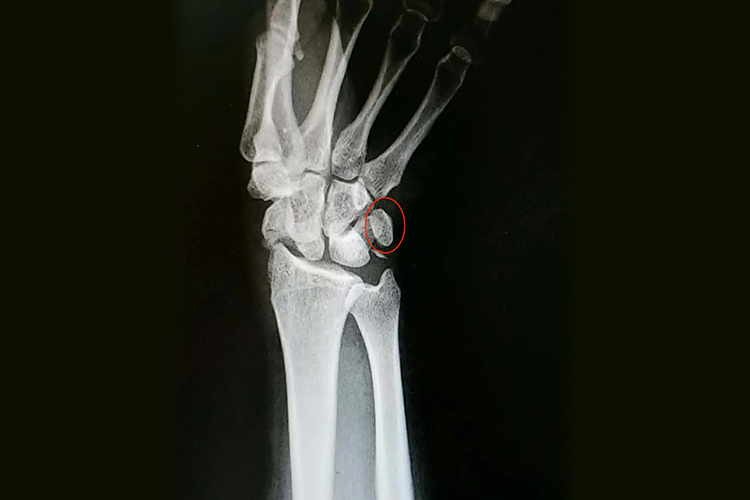

手腕豆状骨的形状像一颗豆子,疏松地与三角骨的掌面联结。

手腕豆状骨的形状像一颗豆子,疏松地与三角骨的掌面联结。豆状骨容易移动也容易触诊,它被镶嵌于尺侧腕屈肌的肌腱,具有种籽骨的特征。